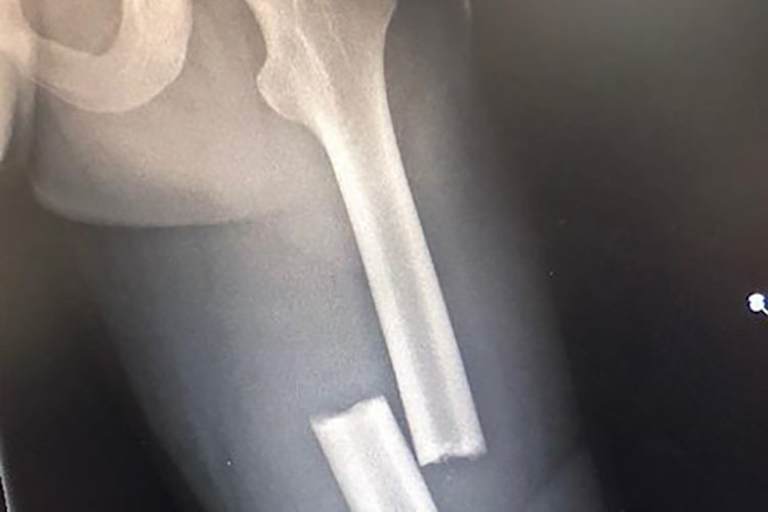

Dupasquier sicherte sich Startplatz 9, doch zur Mitte des ersten Rennens stürzte der Nachwuchspilot schwer. "Ich lag lange Zeit in Spanien und der Schweiz im Krankenhaus, denn beim Rennen der Junioren-WM in Valencia stürzte ich zur Rennmitte und zog mir einen Bruch des Oberschenkelknochens zu. Ich war sehr traurig, denn das waren auch schlechte Nachrichten für die Sponsoren und das ganze Team", schreibt Dupasquier in seinem Blog. "Ich wurde im Krankenhaus von Valencia operiert, der Eingriff verlief erfolgreich. Am Freitag nach dem Rennen wurde ich zurück in die Schweiz gebracht." Auf diese Weise verpasste Dupasquier die ersten beiden Rennwochenenden des Red Bull Rookies Cups in Jerez und Mugello. Mittlerweile befindet sich Dupasquier auf dem Weg der Besserung. "Ich bin nun wieder in Ordnung und werde stärker zurückkommen", versicherte er. Dupasquier hofft nun beim nächsten Rennwochenende des Red Bull Rookies Cups in Assen von 30. Juni bis 1. Juli wieder antreten zu können.